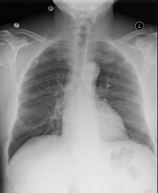

In contrast to manually annotated labels, textual imaging reports, which are often readily available in medical records, contain interpretations written by experts as part of standard clinical practice (Figure 1). These unstructured textual data provide rich information about the images, but it is difficult to directly integrate the data into CNN training as labels.

Refer to caption

FINAL REPORT

HISTORY:

___-year-old female with chest pain.

COMPARISON: Comparison is made with chest radiographs from ___.

FINDINGS: The lungs are well expanded. A retrocardiac opacity is seen which is likely due to atelectasis although infection is hard to exclude. Given the linear shape of the opacity, atelectasis is perhaps more likely. The heart is top-normal in size. The cardiomediastinal silhouette is otherwise unremarkable. There is no pneumothorax or pleural effusion.  Visualized osseous structures are unremarkable.

IMPRESSION: Retrocardiac opacity, likely due to atelectasis but possibly due to pneumonia in the appropriate setting.

Figure 1: An example of a chest x-ray (left) with the radiology report (right) from the MIMIC-CXR dataset.